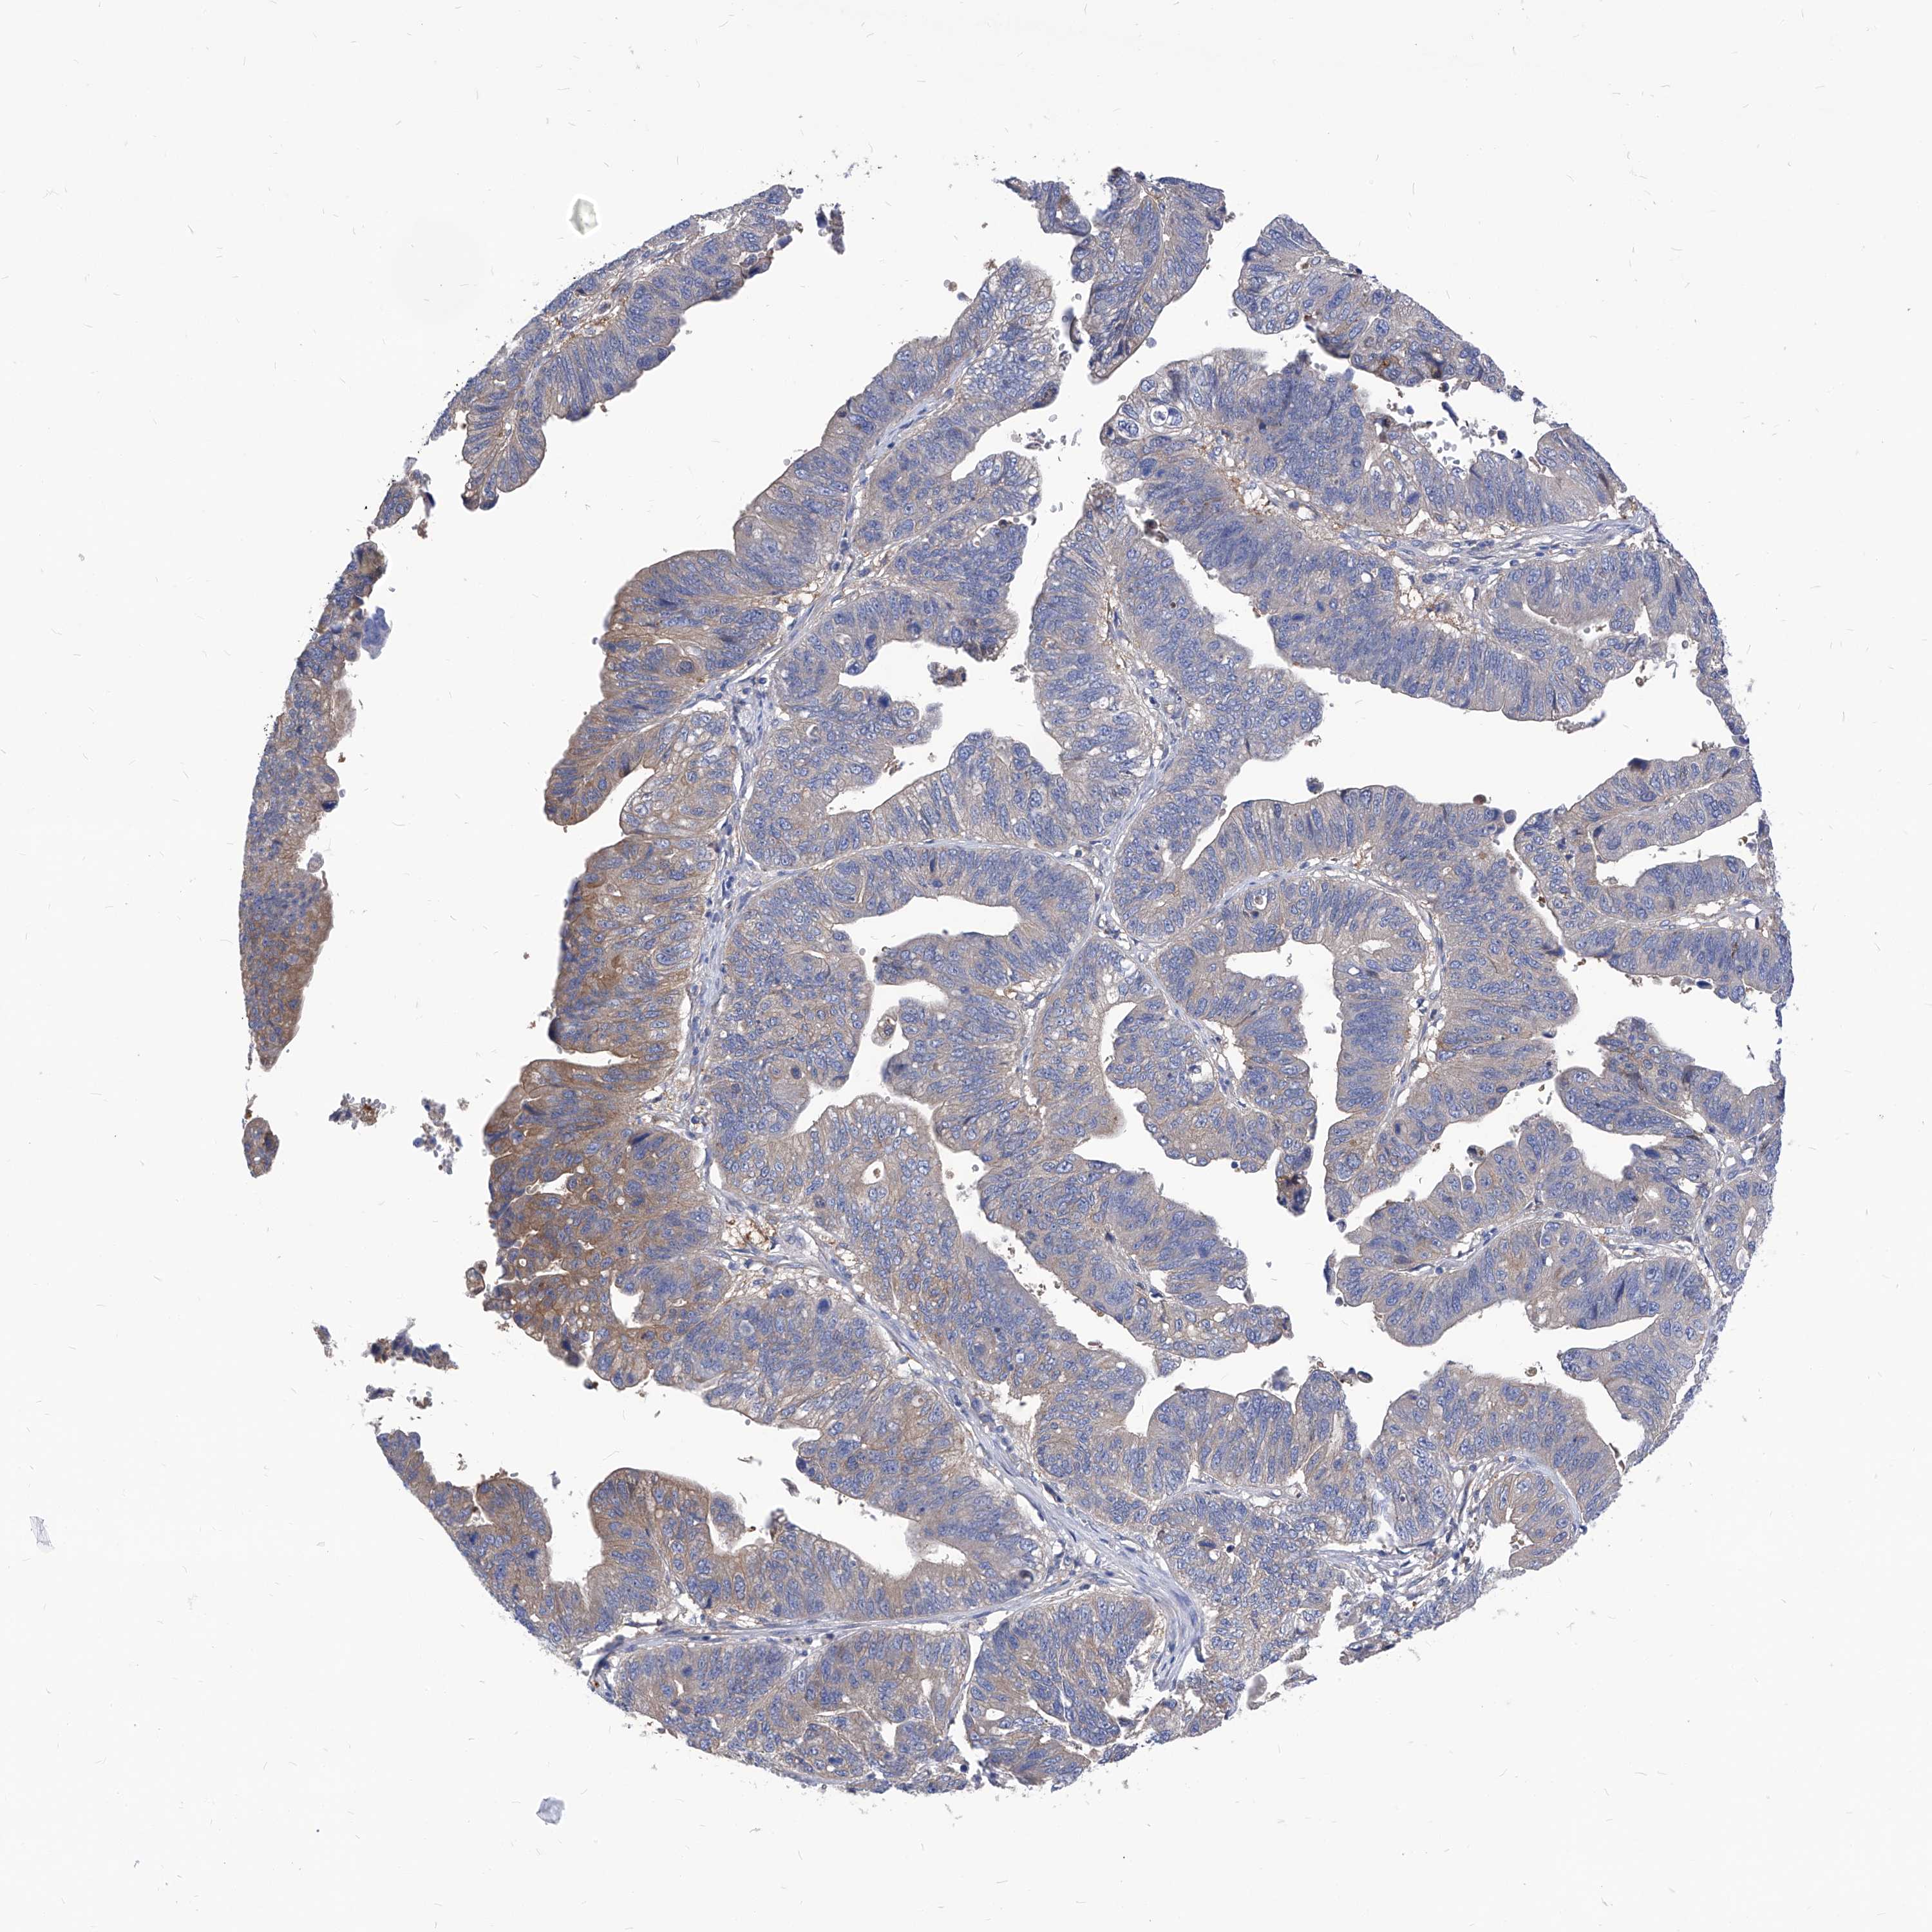

STOMACH CANCER - Protein expressioni

A mouse-over function shows sample information and annotation data. Click on an image to view it in a full screen mode. Samples can be filtered based on level of antibody staining by selecting one or several of the following categories: high, medium, low and not detected. The assay and annotation is described here.

Note that samples used for immunohistochemistry by the Human Protein Atlas do not correspond to samples in the TCGA dataset.

Antibody stainingi

Antibody staining in the annotated cell types in the current human tissue is reported as not detected, low, medium, or high, based on conventional immunohistochemistry profiling in selected tissues. This score is based on the combination of the staining intensity and fraction of stained cells.

Each image is clickable and will lead to virtual microscopy that enables deeper exploration of all samples and also displays staining intensity scores, fraction scores and subcellular localization as well as patient and tissue information for each sample.

HPA030419

HPA030420

HPA030422

CAB025196

CAB080286

CAB080287

Staining

High

Medium

Low

Not detected

Intensity

Strong

Moderate

Weak

Negative

Quantity

>75%

75%-25%

<25%

None

Location

Nuclear

Cytoplasmic/membranous

Cytoplasmic/membranous,nuclear

Adenocarcinoma, NOS

Adenocarcinoma, High grade